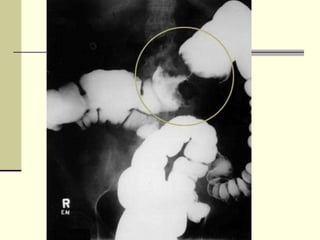

Hyperspasticity of the rectum (arrow), transition zone, and  a rectosigmoid ratio less than 1. S = sigmoid, R = rectum

Hyperspasticity of therectum (arrow), transition zone, and a rectosigmoid ratio less than 1. S = sigmoid, R = rectum